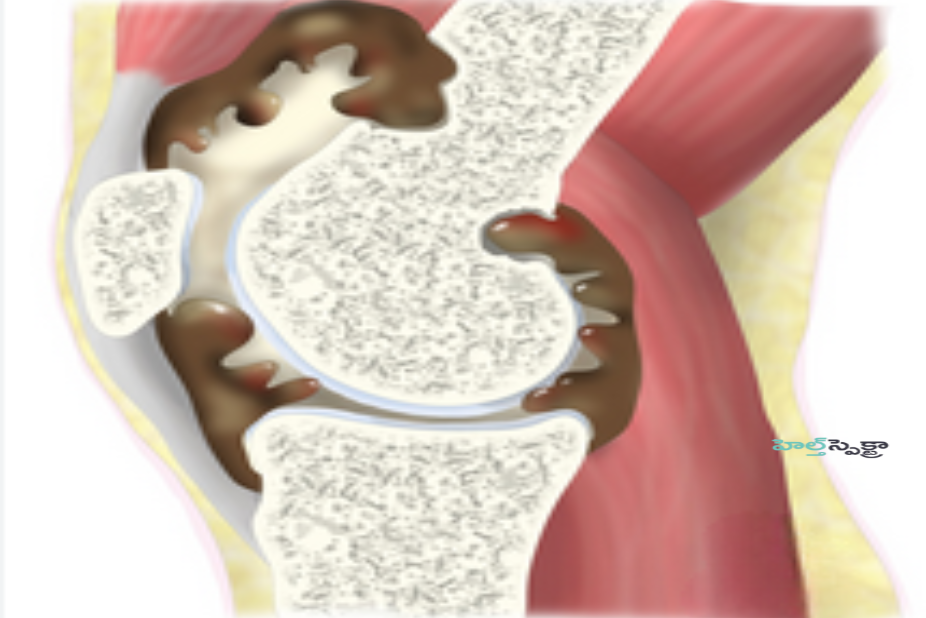

వైద్యులు పిగ్మెంటెడ్ విల్లోనోడ్యులర్ సైనోవైటిస్ (PVNS)ను కీలు లేదా స్నాయువు (సైనోవియం) యొక్క లైనింగ్ చాలా మందంగా పెరిగి సమస్యలను కలిగించే స్థితిగా నిర్వచించారు. సైనోవియం యొక్క ఈ పెరుగుదల అసాధారణ కణజాలం లేదా కణితిని సృష్టిస్తుంది. ఈ కణితి నిరపాయకరమైనది (క్యాన్సర్ లేనిది) మరియు మీ శరీరంలోని ఇతర భాగాలకు వ్యాపించదు. కానీ ఇది కాలక్రమేణా మరింత తీవ్రమవుతుంది, ఎముకను నాశనం చేస్తుంది మరియు మీ జీవన నాణ్యతకు అంతరాయం కలిగిస్తుంది. పిగ్మెంటెడ్ విల్లోనోడ్యులర్ సైనోవైటిస్ (PVNS) కూడా వాపుకు కారణమవుతుంది. సాధారణ కీలులో, సైనోవియం ద్రవాన్ని తయారు చేస్తుంది, ఇది కీలు సజావుగా ముందుకు వెనుకకు కదలడానికి సహాయపడుతుంది.

PVNS అనేది సైనోవియం యొక్క పెరుగుదల మరియు గట్టిపడటం వలన సంభవిస్తుంది. సైనోవియం, దీనిని సైనోవియల్ లైనింగ్ అని కూడా పిలుస్తారు, ఇది కీలును చుట్టుముట్టే సన్నని గుళిక మరియు సైనోవియల్ ద్రవం అనే కందెన ద్రవాన్ని ఉత్పత్తి చేస్తుంది. శరీరంలోని అన్ని కదిలే కీళ్లలో సైనోవియం ఉంటుంది, ఇది కీలు కదులుతున్నప్పుడు కీలు నిర్మాణాలలో ఘర్షణను తగ్గిస్తుంది. PVNS వల్ల కలిగే అసాధారణ సైనోవియల్ లైనింగ్ కీళ్ల వాపుకు దారితీస్తుంది, కొన్నిసార్లు కదలికకు అంతరాయం కలిగిస్తుంది మరియు తీవ్రమైన సందర్భాల్లో ఎముకతో సహా సమీపంలోని కీళ్ల నిర్మాణాలలోకి పెరిగి నాశనం చేయవచ్చు.